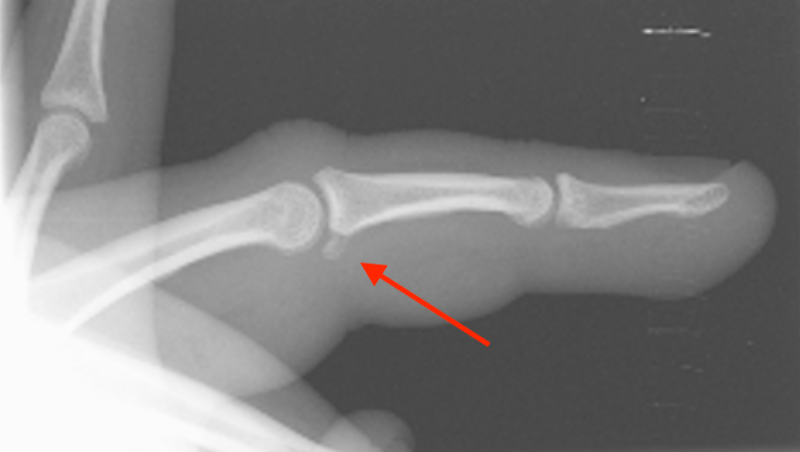

2. Obtain post-reduction x-rays

- If there is associated volar (arrow above) or dorsal plate fractures, refer to our associated cases for management: Hand Case 12